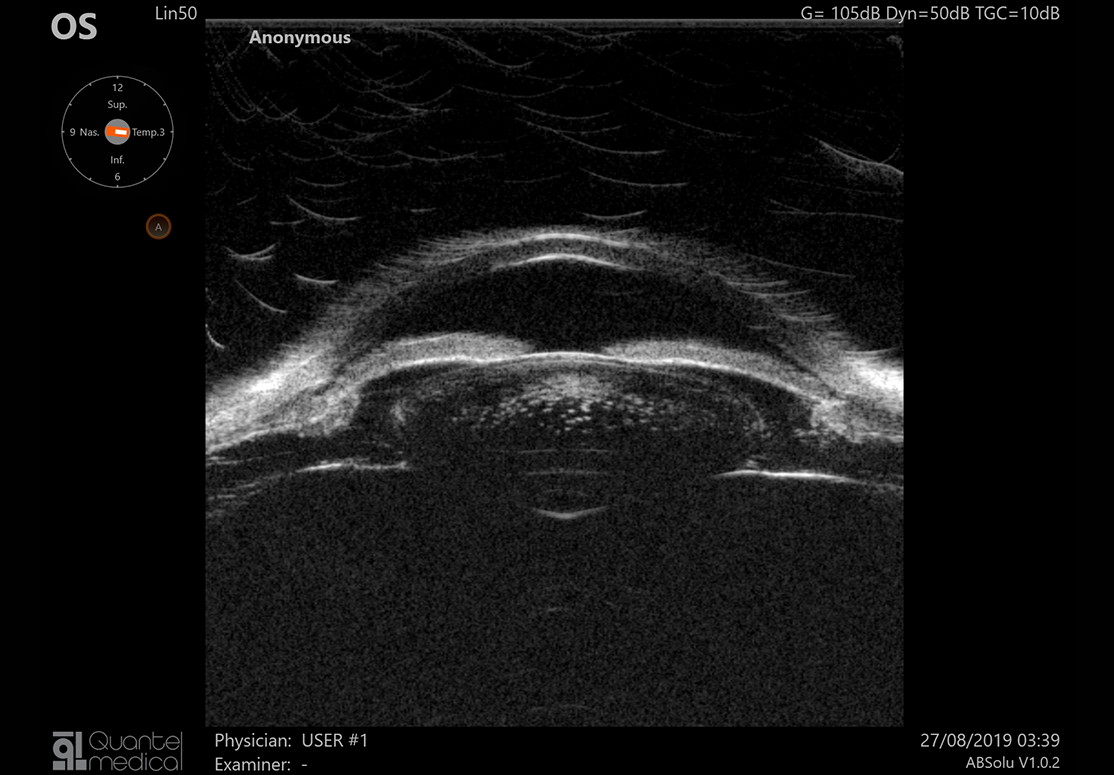

A / B / S / UBM Ultrazvuková platforma

Quantel Medical udělal významný kvalitativní krok vpřed, když vyvinul 20 MHz annulární sondu pro dokonalou kvalitu obrazu v celé délce oka. Princip spočívá ve vysílání ultrazvukového signálu pomocí pěti soustředných měničů umístěných v sondě, díky tomu získáte opravdu působivé snímky celého oka s výjimečnou úrovní detailu.

Nová zobrazovací technologie UBM umožňující různé režimy zobrazování

• 50 MHz UBM sonda pro přední segment